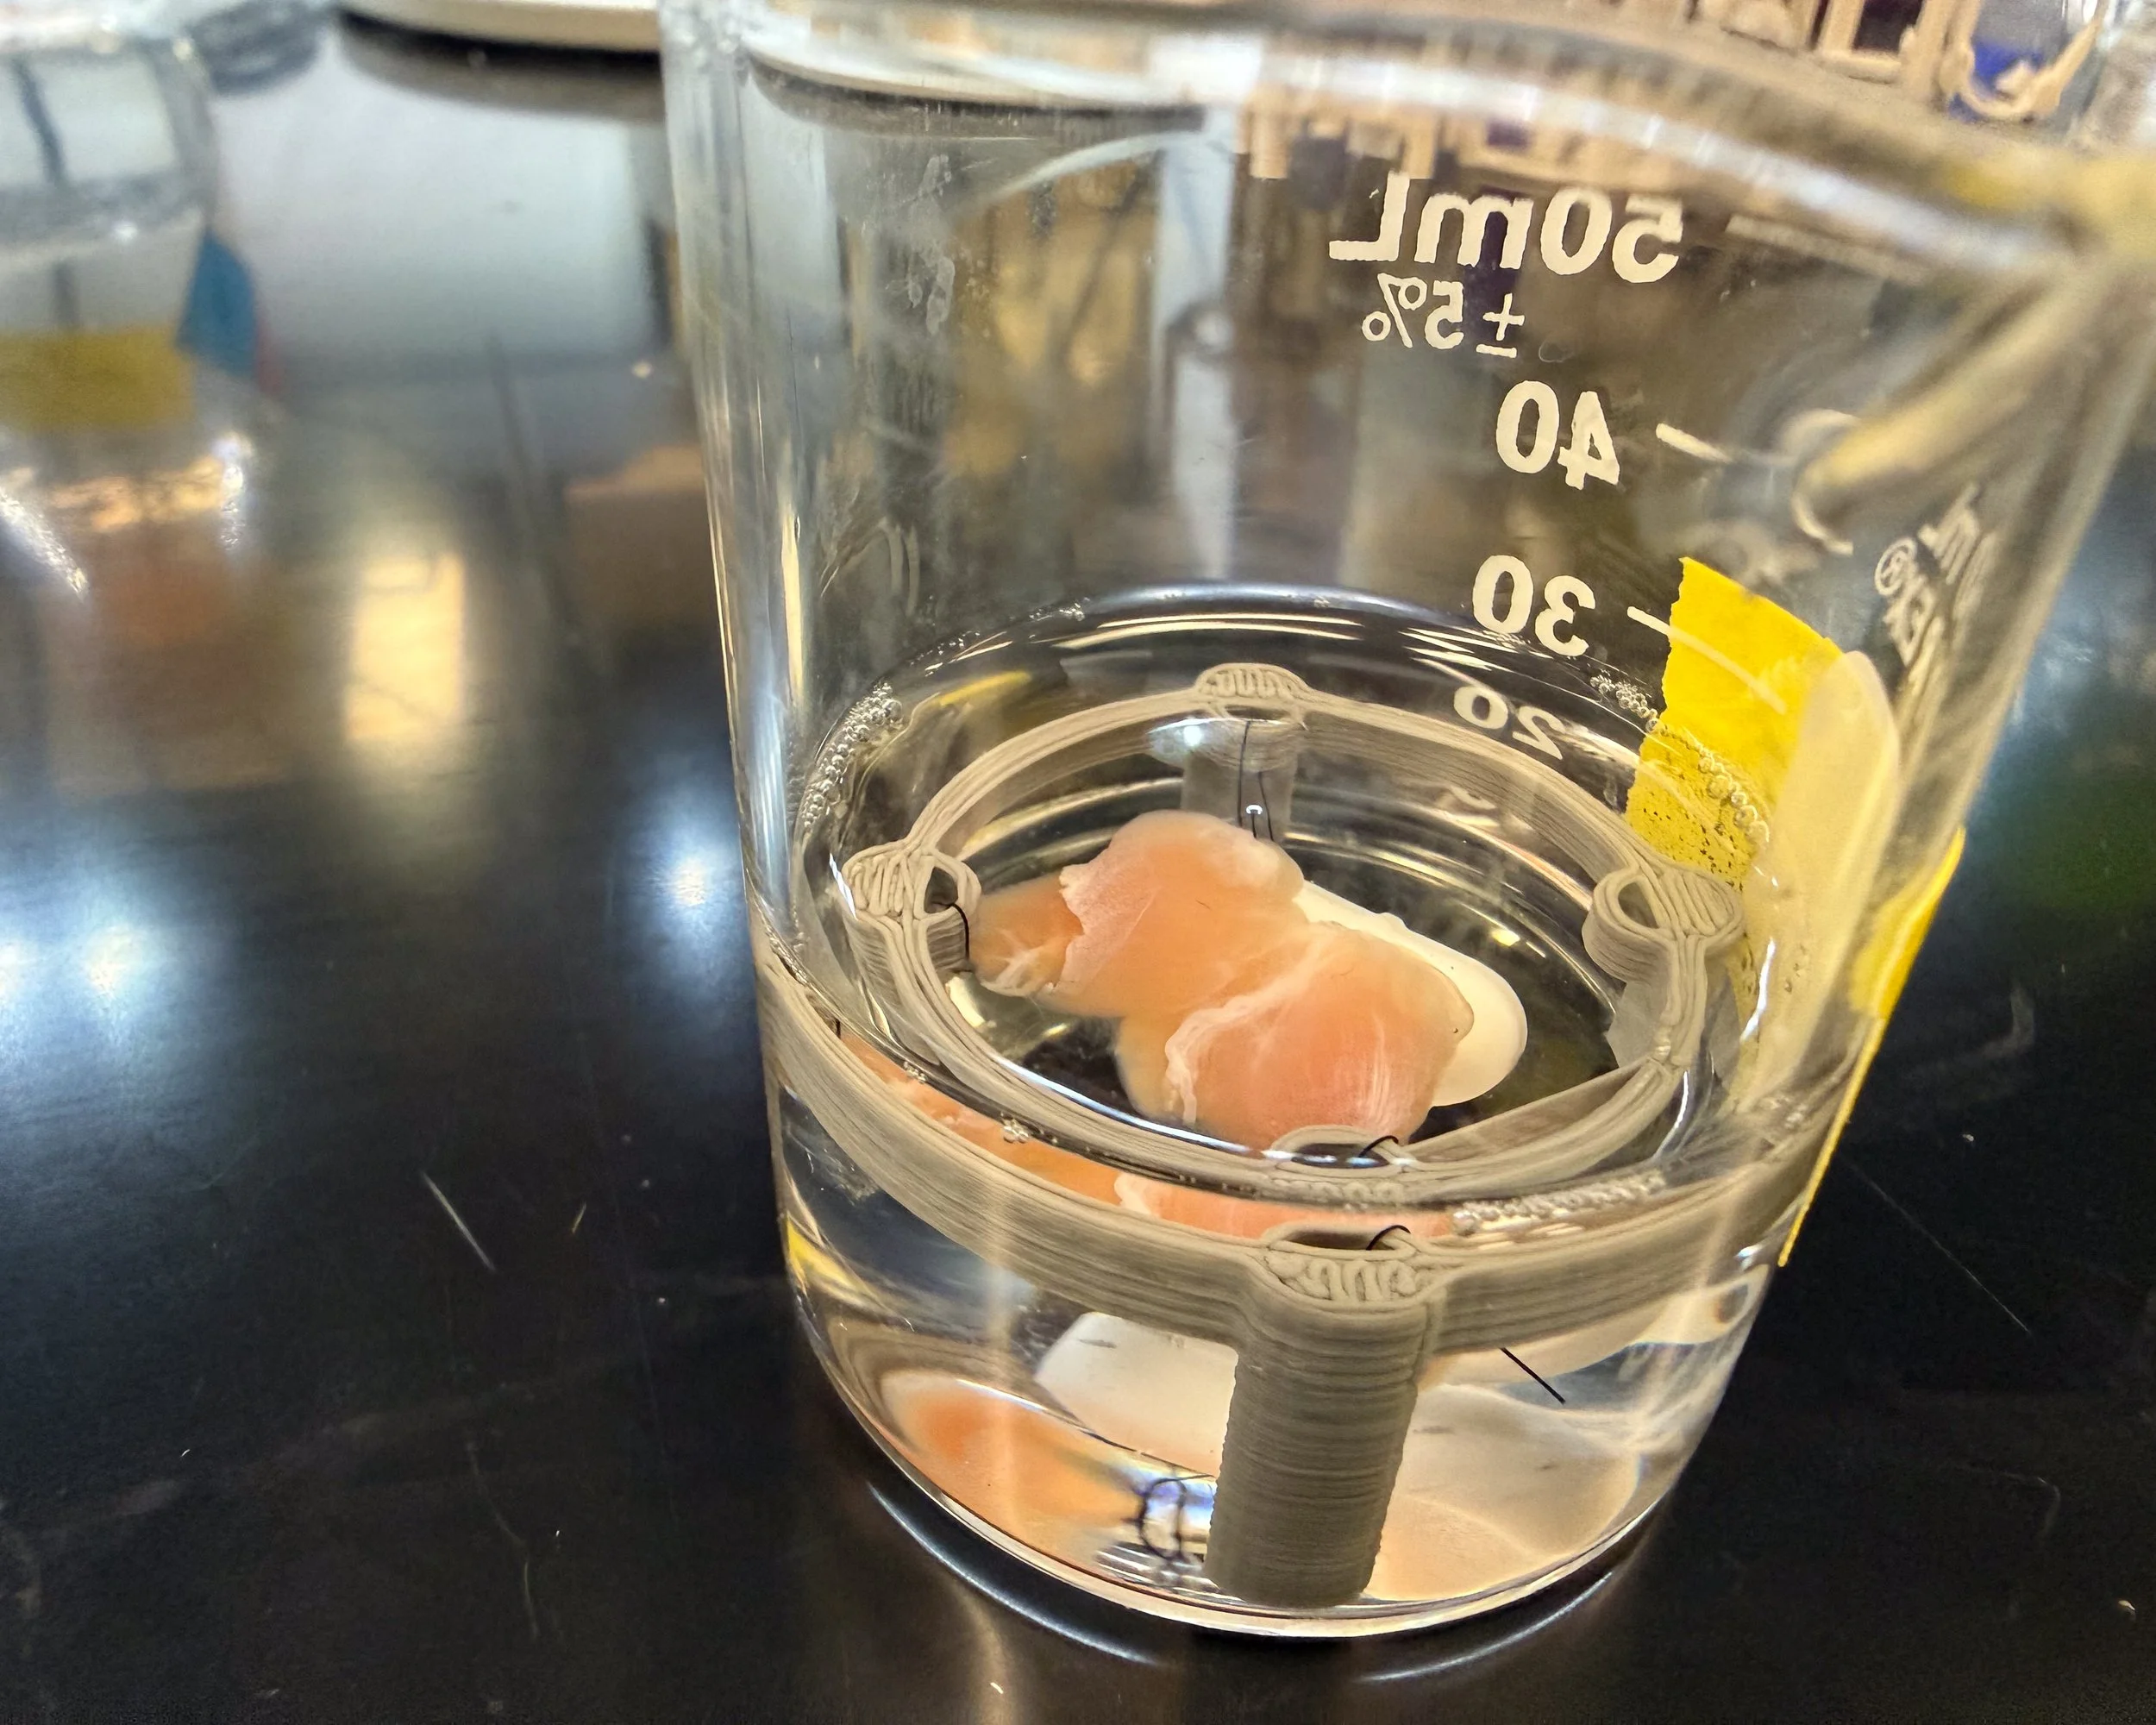

Gallery: DMM in development at the Sarcogenics lab

Remove cells, keep structure

Donor muscle tissue is processed to strip away all living cells, leaving behind the extracellular matrix — a natural scaffold made of proteins like collagen, laminin, and fibronectin.